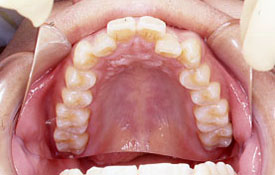

インビザラインの治療例:CASE-1

| プロフィール | 42歳 女性 |

| 所見 | 他院で行われた矯正歯科治療後の後戻りに悩まれて来院されました。 アイライナーの装着は、1日平均20時間ほどでした。 |